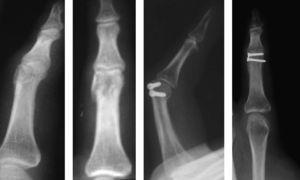

Para llevar a cabo esta técnica se realizó una selección según las características de los pacientes y el tipo de fractura. Es imprescindible que sean pacientes colaboradores y las fracturas subsidiarias de este tipo de tratamiento fueron fracturas inestables que permitían conseguir una buena estabilidad mediante la osteosíntesis con tornillos, como fracturas condíleas de las falanges, fracturas diafisarias espiroideas u oblicuas largas de la falange, fracturas de la base de la falange, fracturas intraarticulares y algunas fracturas de la base del primer metacarpiano (figura 1,figura 2,figura 3,figura 4).

Figura 4. Fractura de la base del primer metacarpiano.